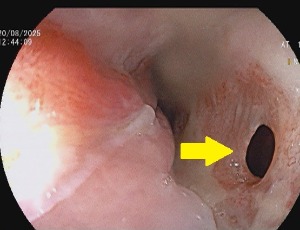

Bouveret’s syndrome is a rare condition characterized by gastric outlet obstruction from an ectopic gallstone, facilitated by aberrant connection of the biliary and luminal gastrointestinal tracts. Establishing a diagnosis of Bouveret’s syndrome can be aided by clinical, radiologic, and endoscopic assessments and importantly relies on prompt diagnosis and management. Despite its rarity, the disease confers a high rate of morbidity and mortality.